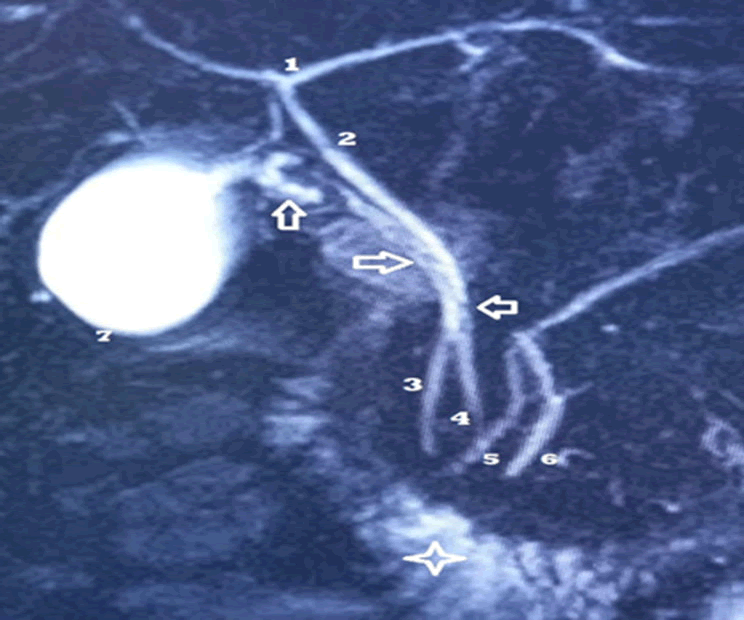

Figure 1. Bili-MRI of Miss O. Rachel. T2 HASTE 3D (MRI cholangiography).

The intrahepatic biliary confluence where an accessory cystic duct ends ensuring vesicular filling [1].

The common bile duct [2,3] with a regular wall without endoluminal defect is normal.

The gallbladder (7) is drained by another so-called main cystic duct (hollow arrows and 4) which crosses the main pancreatic duct to merge with the accessory pancreatic duct [5]. Note the disparities in caliber of the main cystic duct on the upper 2/3 of its course with multiple defects in relative hyposignal which may correspond to endoluminal mucosal folds of the cystic duct. No clear stone signal.